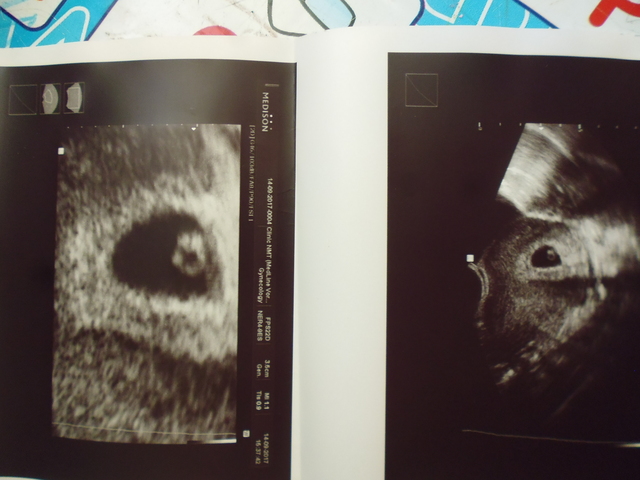

УУУУУРА!!! тест заполосатил, на УЗИ подтвердили акушерский срок 3-4 недели!! мечтаю о дочке!!! вчера встала на учет  три часа в больнице  есть еще кто-то, кто уже знает о своем прекрасном положении??? НАШИ НЕДЕЛЬКИ

Natalie1505, Holy-ganka, Спасибо девочки. Сегодняшний ХГЧ 198 Завтра на УЗИ.

Holy-ganka, видно, видно. У меня уже есть УЗи 2,2 мм. И пред идущая беременность, на 3 день задержки прекрасно видно. Только врач тожен быть опытный, аппарат хороший, и желание врача сделать не на об***сь... Я на самом деле хочу убедится что беременность маточная, что мой сантиметровый миоматозный узел не там где малыш прикрепился. И все. Понятно что кроме микропузырька там ничего не найдут. Просто у меня УЗИ под боком. В его вред я не верю. По этому трудно удержатся от соблазна.

Нина_Nina, сходила на узи? Как у тебя дела? привет! сходила на узи в четверг. Все у нас хорошо, эмбрион и сердечко